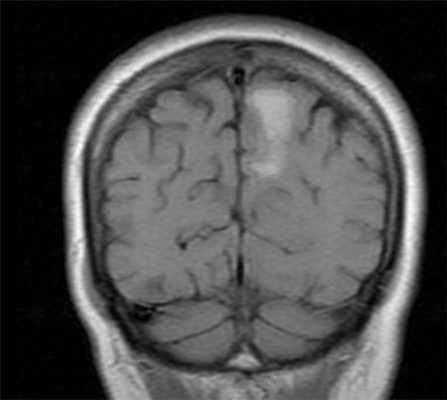

МРТ головного мозга. Т1-взвешенная корональная МРТ. Смешанный ишемический инсульт. Ранняя подострая стадия.